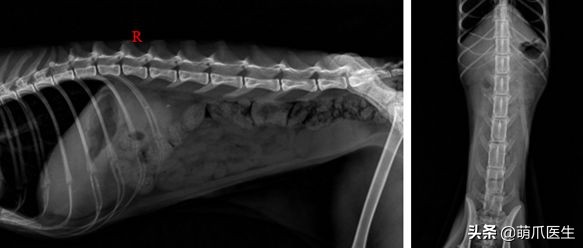

一只布偶猫的x光检查,显示双侧肾脏肿大